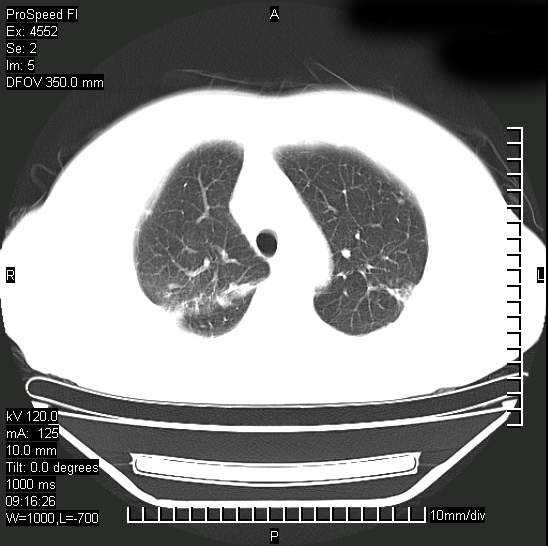

今天ct

短短几天内,病变范围明显增多扩大,以左侧明显,而且双侧出现胸水,还是考虑感染.

短短几天内,病变范围明显增多扩大,以左侧明显,而且双侧出现胸水,我更多考虑左侧中心性肺癌并并阻塞性不张及肺炎,炎症变化也太快了!

无论是肿瘤还是炎症4天的时间都发展够快的,并且还在治疗中,如果说是左肺癌那么右肺的病变不好解释,本人更加倾向于炎症,左肺舌叶支气管被痰栓或血凝块堵塞,造成阻塞性肺炎。

1)两肺结核并感染。2)不排除左肺上叶中央型肺癌并阻塞性肺炎、肺不张可能;建议行纤支镜检查。3)右肺门及纵隔淋巴结肿大。4)双侧胸腔积液。